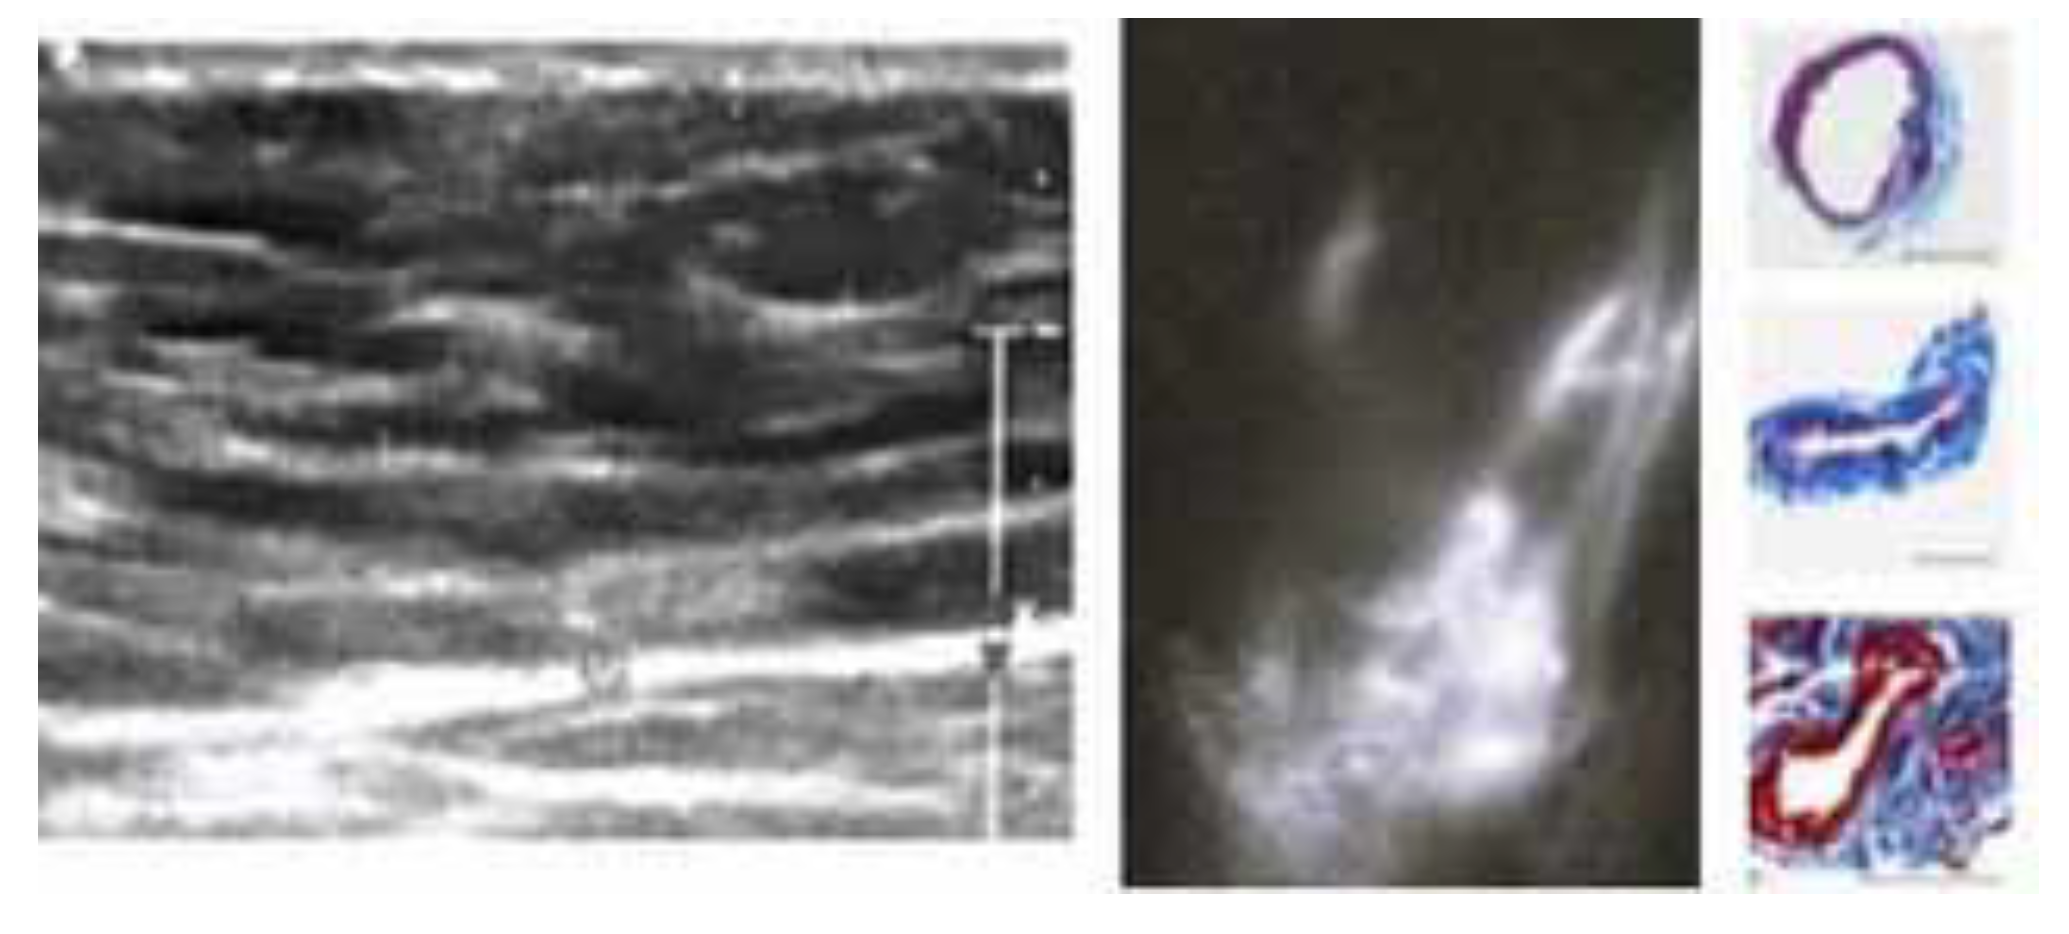

- Weber, E.; Aglianò, M.; Bertelli, E.; Gabriele, G.; Gennaro, P.; Barone, V. Lymphatic Collecting Vessels in Health and Disease: A Review of Histopathological Modifications in Lymphedema. Lymphat. Res. Biol. 2022, 20, 468–477. [Google Scholar] [CrossRef] [PubMed] [PubMed Central]

- Mihara, M.; Hara, H.; Hayashi, Y.; Narushima, M.; Yamamoto, T.; Todokoro, T.; Iida, T.; Sawamoto, N.; Araki, J.; Kikuchi, K.; et al. Pathological steps of cancer-related lymphedema: Histological changes in the collecting lymphatic vessels after lymphadenectomy. PLoS ONE 2012, 7, e41126, Erratum in PLoS ONE 2013, 8. [Google Scholar] [CrossRef] [PubMed] [PubMed Central]

- Barone, V.; Borghini, A.; Tedone Clemente, E.; Aglianò, M.; Gabriele, G.; Gennaro, P.; Weber, E. New Insights into the Pathophysiology of Primary and Secondary Lymphedema: Histopathological Studies on Human Lymphatic Collecting Vessels. Lymphat. Res. Biol. 2020, 18, 502–509. [Google Scholar] [CrossRef] [PubMed]